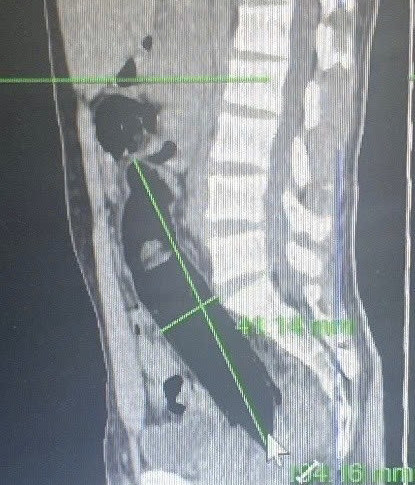

Hình ảnh dị vật trên phim chụp. Ảnh: BSCC.

Bệnh viện đã tiến hành chiếu chụp cắt lớp vi tính đánh giá vị trí dị vật và nội soi đại trực tràng để gắp dị vật. Qua phim chụp, bác sĩ cũng hoảng vì dị vât quá lớn chèn vào đường tiêu hóa.